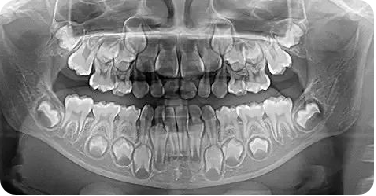

牙齿就如同一颗种子,在我们的上下颌骨内“生根发芽”。人的第一副牙齿就是婴儿时期的乳牙,随着正常的生长发育,乳牙逐渐被吸收替换,形成了人类的第二副牙齿,也是未来陪伴我们时间最长的牙列—恒牙列。乳牙替换为恒牙的过程即为换牙,这段时期也被称之为“替牙期”。孩子换牙是一次蜕变的过程,会面临很多问题,家长也会有很多的疑问,下面我们就为大家整理一些“换牙期的那些事”。

乳牙一般2岁半完全萌出,从6岁左右开始换牙,进入替牙期,期间会将孩子口腔内的20颗乳牙全部替换为恒牙,另外还会新长出8颗恒磨牙。换牙通常会持续到12岁左右,因孩子生长发育情况不同,时间也可能有差异,但这些恒牙长出后将不再替换,所以要好好保护哦!

一般情况下乳牙正常脱落后,2-3个月恒牙即可萌出。当乳牙脱落很长时间,恒牙仍未见萌出,就需要到专业医疗机构拍摄X线片,查看是否有恒牙胚。如有恒牙胚,且牙根发育正常,可继续观察,必要时可行切开助萌。